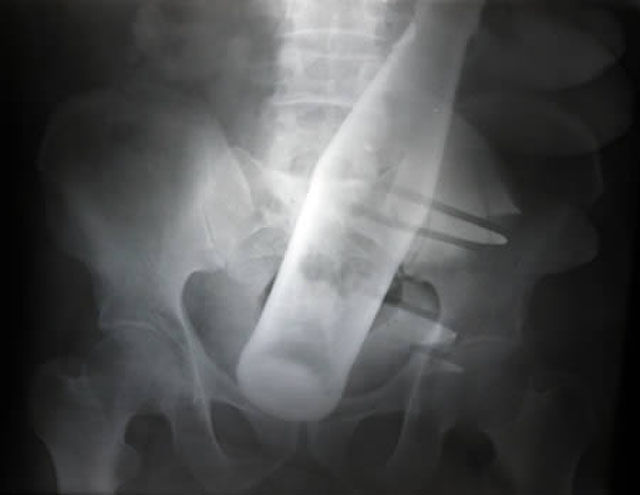

This X-ray was taken of a 60-year-old man who checked himself into Nishtar Hospital in Multan, Pakistan. He sought treatment because he claimed thieves had inserted a Pepsi bottle into his anus before stealing two of his buffalo.

A Chinese man was complaining of stomach pains.The man, was forced to seek medical help after failing to extract a bottle with a curved piece of wire. When medical staff quizzed him on the pain, he claimed he did not know what was causing his discomfort.But he suddenly remembered what had happened when staff presented him with clear X-rays showing the bottle and wire inside of him. He admitted inserting the bottle at home before it became stuck and said he used a steel wire in an attempt to get it back out in a moment of panic.